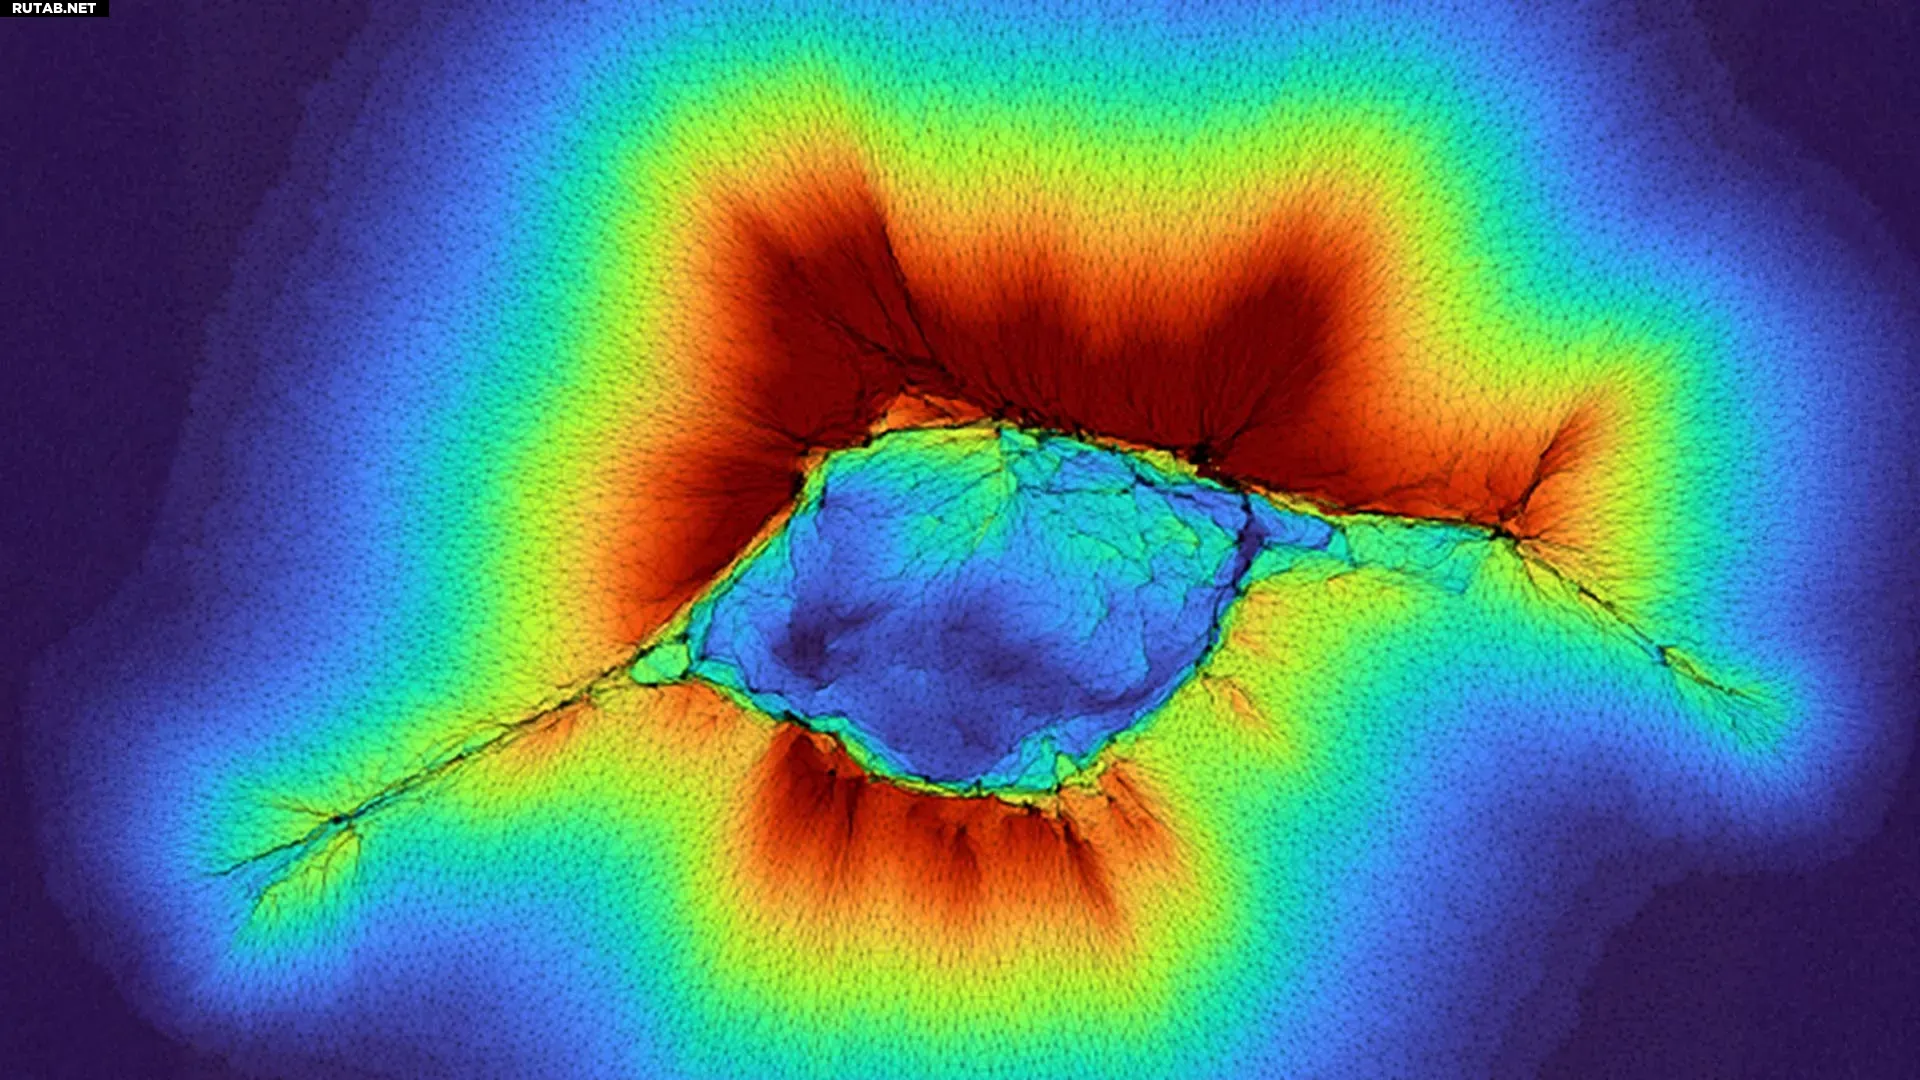

Оказалось, что группы эпителиальных клеток, формирующих поверхности тканей, генерируя совместное усилие, способны «прощупывать» коллагеновые волокна и обнаруживать слои на расстоянии до 100 микрон. Как объяснил профессор Амит Патхак, «поскольку это коллектив клеток, они генерируют более высокие силы».